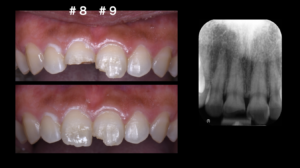

さて、今回は中切歯(#8と#9)が破折していました。幸い脱臼もなく、露髄もなく、神経も正常な反応がありました。#8に関しては、持参した破折片がしっかり歯に戻る状態でした。

結論から言うと①の方針で治療を進めることになりました。なぜなら、一番費用対効果が高いからです。特に、#8に関しては、ご自身の歯をもう一度接着させるだけなので削らずに治療ができ、本来の歯の形態に戻すことができます。もちろん、再度とれてしまうこともリスクとしてはありますが、患者様は開口という歯並びのため、あまり前歯に負担がかからない歯並びをされていました。従って、通常より破折のリスクは低いでしょう。また、露髄もなくレジンセメントと優れた化学的接着が可能なエナメル質が残っているのも一つの要因です。優れた接着力を期待できます。②と③に比べ、かかる費用も安いです。

実際の治療では、ラバーダム防湿後に#8の破折片と歯にサンドブラスティングを施行。リン酸でエッチングをして、第4世代のトータルエッチングシステムを用いて、レジンセメントにて接着させました。#9も通常通り前処理後にレジン充填にて修復しました。切端の特徴的な段差もできるようにデザインしました。